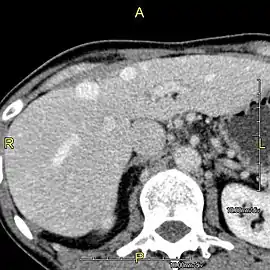

Axial CT image showing anomalous hepatic veins coursing on the liver's subcapsular anterior surface[70]

Maximum intensity projection (MIP) CT image as viewed anteriorly showing the anomalous hepatic veins coursing on the anterior surface of the liver

Lateral MIP view in the same patient as previous image

A CT scan in which the liver and portal vein are shown